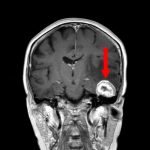

良性頭蓋咽頭腫

頭蓋内腫瘍摘出術

No.’25_113 手術前1

No.’25_113 手術前2